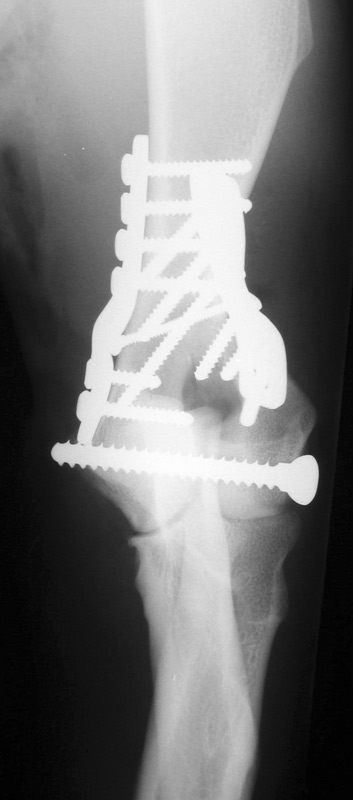

• multi-modal fracture repair

(please click on photos to enlarge)